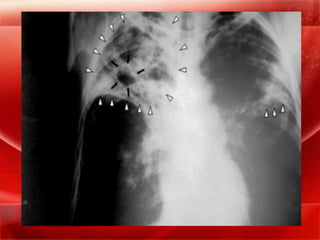

TUBERCULOSIS PULMONAR

La tuberculosis pulmonar puede ser :

Primaria

Postprimaria (secundaria).

TUBERCULOSIS PRIMARIA

La tuberculosis pulmonar primaria es la que

aparece consecutivamente a la infección inicial

por el bacilo tuberculoso.

TUBERCULOSIS SECUNDARIA

Llamada también tuberculosis secundaria, de

reactivación, o de tipo adulto.